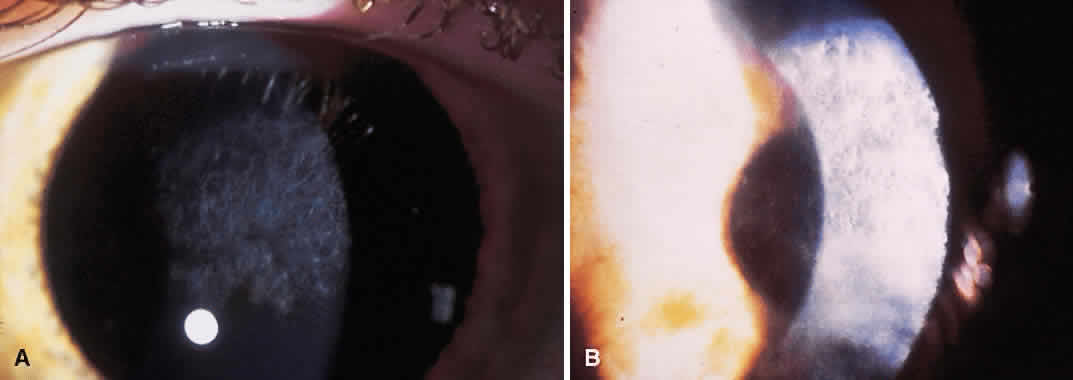

Current techniques have evolved to eliminate most of these complications. The diamond blades used today have two cutting edges. The main cutting edge is sharp for the entire length of the blade, whereas the anterior surface has a cutting surface for only 250 μm (Fig. 1). The blunt portion of the blade helps prevent inadvertent encroachment of the visual axis. Also, the new blades have a housing that will glide along the corneal surface to help keep the incisions perpendicular.